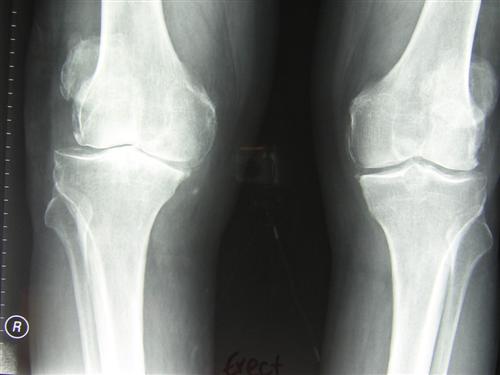

UKA lateral fixed bearing

Lateral compartmental knee replacement with a fixed bearing prosthesis (such as the Miller-Gallante) is a good method of dealing with end-stage, bone-on-bone predominantly lateral compartment osteoarthrosis of the knee. This because of the documented favorable immediate and long term outcome. In this operation, only the 'worn-out' part of the knee is replaced, the remainder of the knee is left alone. Prerequisites for a good long term outcome are preservation of the medial compartment, as demonstrated on X-ray stress views. The importance of cruciate ligaments integrity is uncertain. 90-95% of these prostheses are expected to still function well at 10 years. The number of patients reported on in long-term follow-up studies is less than for medial compartmental knee replacement. The 10 years results appear similar to the outcome after total knee replacement. For the 5-10% of patients who have required a revision of the initial knee replacement, either unicompartmental or total, by 10 years, a revision from unicompartmental knee replacement to total knee replacement is easier and will have a better long-term outcome than a revision from total to total knee replacement. Starting with a lateral unicompartmental knee replacement under well-defined conditions, may yield a longterm outcome similar to total knee replacement, with less surgical risk and more options for revision than after providing immediate total knee replacement, i.e. 'don't burn the bridges until you have to'.

Pre-operative pictures:

Lateral compartment osteoarthritis: varus stress view

Lateral compartment osteoarthritis: valgus stress view